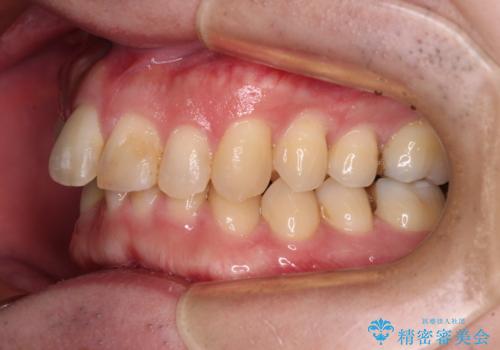

- 深い咬み合わせによる食いしばりで、顎関節や頭が痛むことがあるとのことで来院された患者様です。

歯ぎしりができないくらい強い食いしばりの咬合状態であったため、奥歯の歯軸を起き上がらせることで咬合を挙上させ、歯ぎしりができるようにしていくこととしました。

下顎が左側にずれているため、上下正中は最大限合わせられるところまで合わせるゴールとなりました。